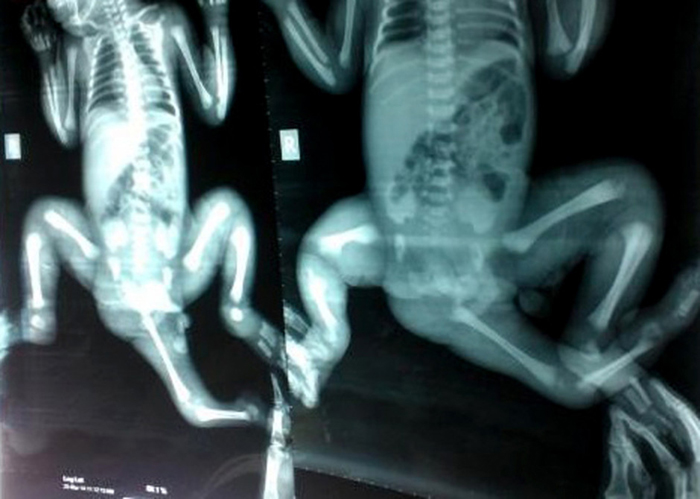

പ്രേതസിനിമകളിലും കഥാപുസ്തകങ്ങളിലും മറ്റുമാണ് മൂന്നുകാലുള്ള മനുഷ്യക്കുറിച്ച് നമ്മൾ കണ്ടിട്ടുള്ളത് എന്നാൽ ജീവിതത്തിൽ മൂന്നു കാലുള്ള ആരെയങ്കിലുംകുറിച്ച് സങ്കൽപ്പിക്കാൻ കഴിയുമോ. സംഭവം സത്യമാണ്. ബംഗ്ലാദേശിലുള്ള ചോയ്റ്റി ഖട്ടൂണ് എന്ന ബാലികയ്ക്കാണ് ഇത്തരത്തിലുള്ള രൂപമാറ്റം സംഭവിച്ചത്. കുട്ടിയുടെ ശരീരത്തിന് അരയ്ക്കു താഴെ നിന്നും മറ്റൊരു അസ്ഥി വളർന്നു വരുന്നതായിരുന്നു പ്രധാന പ്രശ്നമായി മാറിയത്. ഓസ്ട്രേലിയയിൽ നടത്തിയ ശസ്ത്രക്രിയക്കു ശേഷം കുട്ടി ഇപ്പോൾ വീട്ടിലേക്കു മടങ്ങിയെത്തിയിരിക്കുകയാണ്. ഓസ്ട്രേലിയൻ ചാരിറ്റി ചിൽഡ്രൻ ഫസ്റ്റ് ഫൗണ്ടേഷന്റെ ആഭിമുഖ്യത്തിലാണ് കുട്ടിയെ ആശുപത്രിയിൽ എത്തിച്ചത്.

മാസങ്ങൾ നീണ്ടു നിന്ന പദ്ധതിക്കു ശേഷമായിരുന്നു കുട്ടിയെ ശസ്ത്രക്രിയക്കു വിധേയയാക്കിയത്. ഓസ്ട്രേലിയയിൽ എത്തിയപ്പോൾ കുട്ടിക്ക് നടക്കാൻ പോലും കഴിയില്ലായിരുന്നു. ഓപ്പറേഷന് അമേരിക്കയിലെയും യൂറോപ്പിലെയും പ്രശസ്തരായ ഡോക്ടർമാരുടെ ഉപദേശവും തേടിയിരുന്നു. അതിവിദഗ്ധരായ എട്ടു ഡോക്ടർമാരുടെ മേൽനോട്ടത്തിലായിരുന്നു ശസ്ത്രക്രിയ. ഇപ്പോൾ കുട്ടി സുഖംപ്രാപിച്ചു വരികയാണ്.